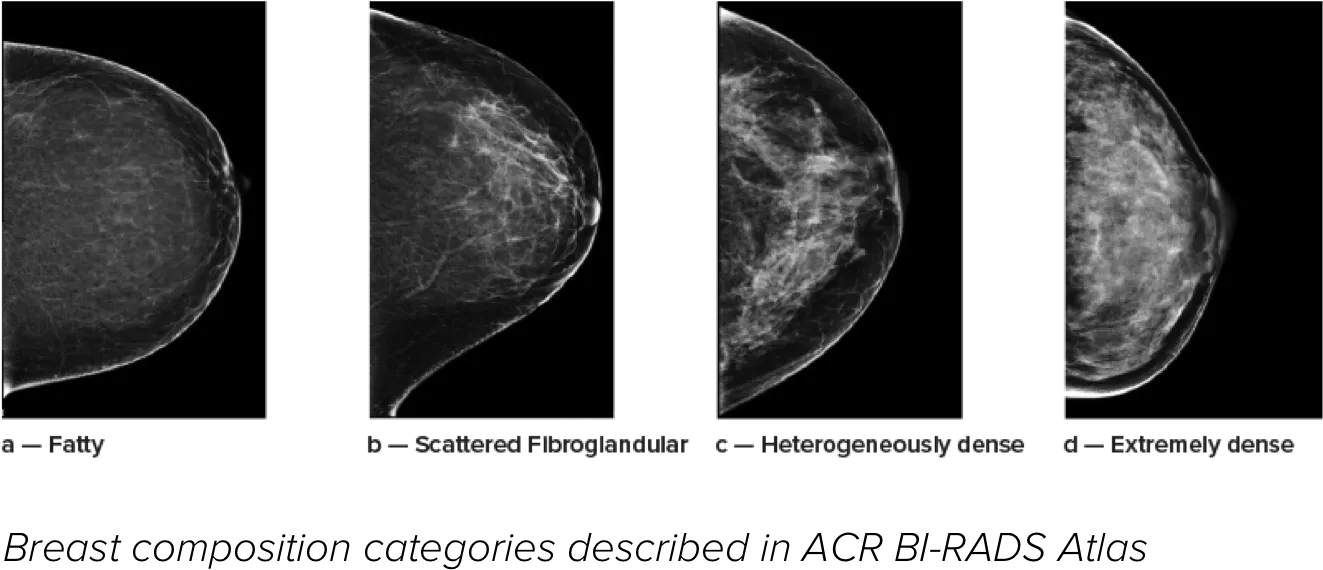

Man ved, at højere brysttæthed øger en kvindes risiko for brystkræft.1 Behovet for nøjagtige, objektive analyser er derfor afgørende. Quantra-teknologisoftwaren er drevet af maskinlæring og analyserer både 2D™ og tomosyntesebilleder for fordeling og tekstur af parenkymvæv. Den kategoriserer bryster i fire brystkompositionskategorier i overensstemmelse med vejledningen fra American College of Radiology (ACR) BI-RADS Atlas 5th Edition.2

* Scorer er baseret på ACR BI-RADS-kategorier på linje med den reviderede vejledning fra American College of Radiation (ACR) BI-RADS Atlas 5th Edition. Dette tager højde for mønster og tekstur i sammenlignet med volumen, når man bestemmer tæthed.

8. Breast composition categories as described in ACR BI-RADS Atlas.